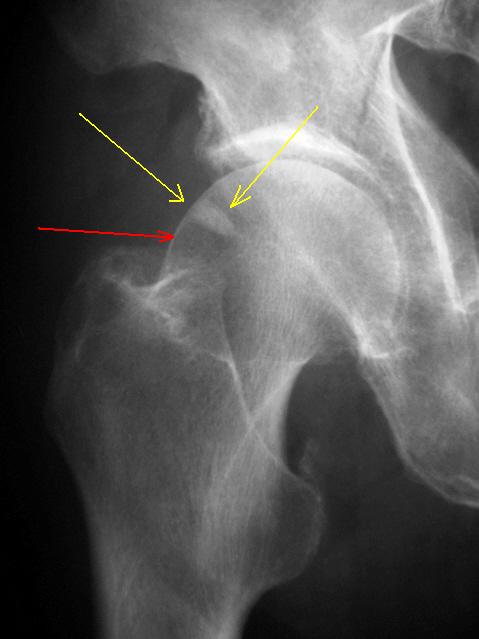

Косой перелом правой тазовой кости без смещения отломков. С момента травмы прошло около 1,5-2,0 месяцев. Пациент направлен "на контрольное исследование".

В верхнем наружном секторе головки бедренной кости визуализируется участок уплотнения вытянутой треугольной формы. Участок помечен желтыми стрелками. Рядом дифференцируется участок просветления - помечен красной стрелкой.

Возник вопрос о субстрате "уплотнения" и "просветления".

УВАЖАЕМЫЕ КОЛЛЕГИ!   Какое Ваше будет мнение по "поводу субстрата".